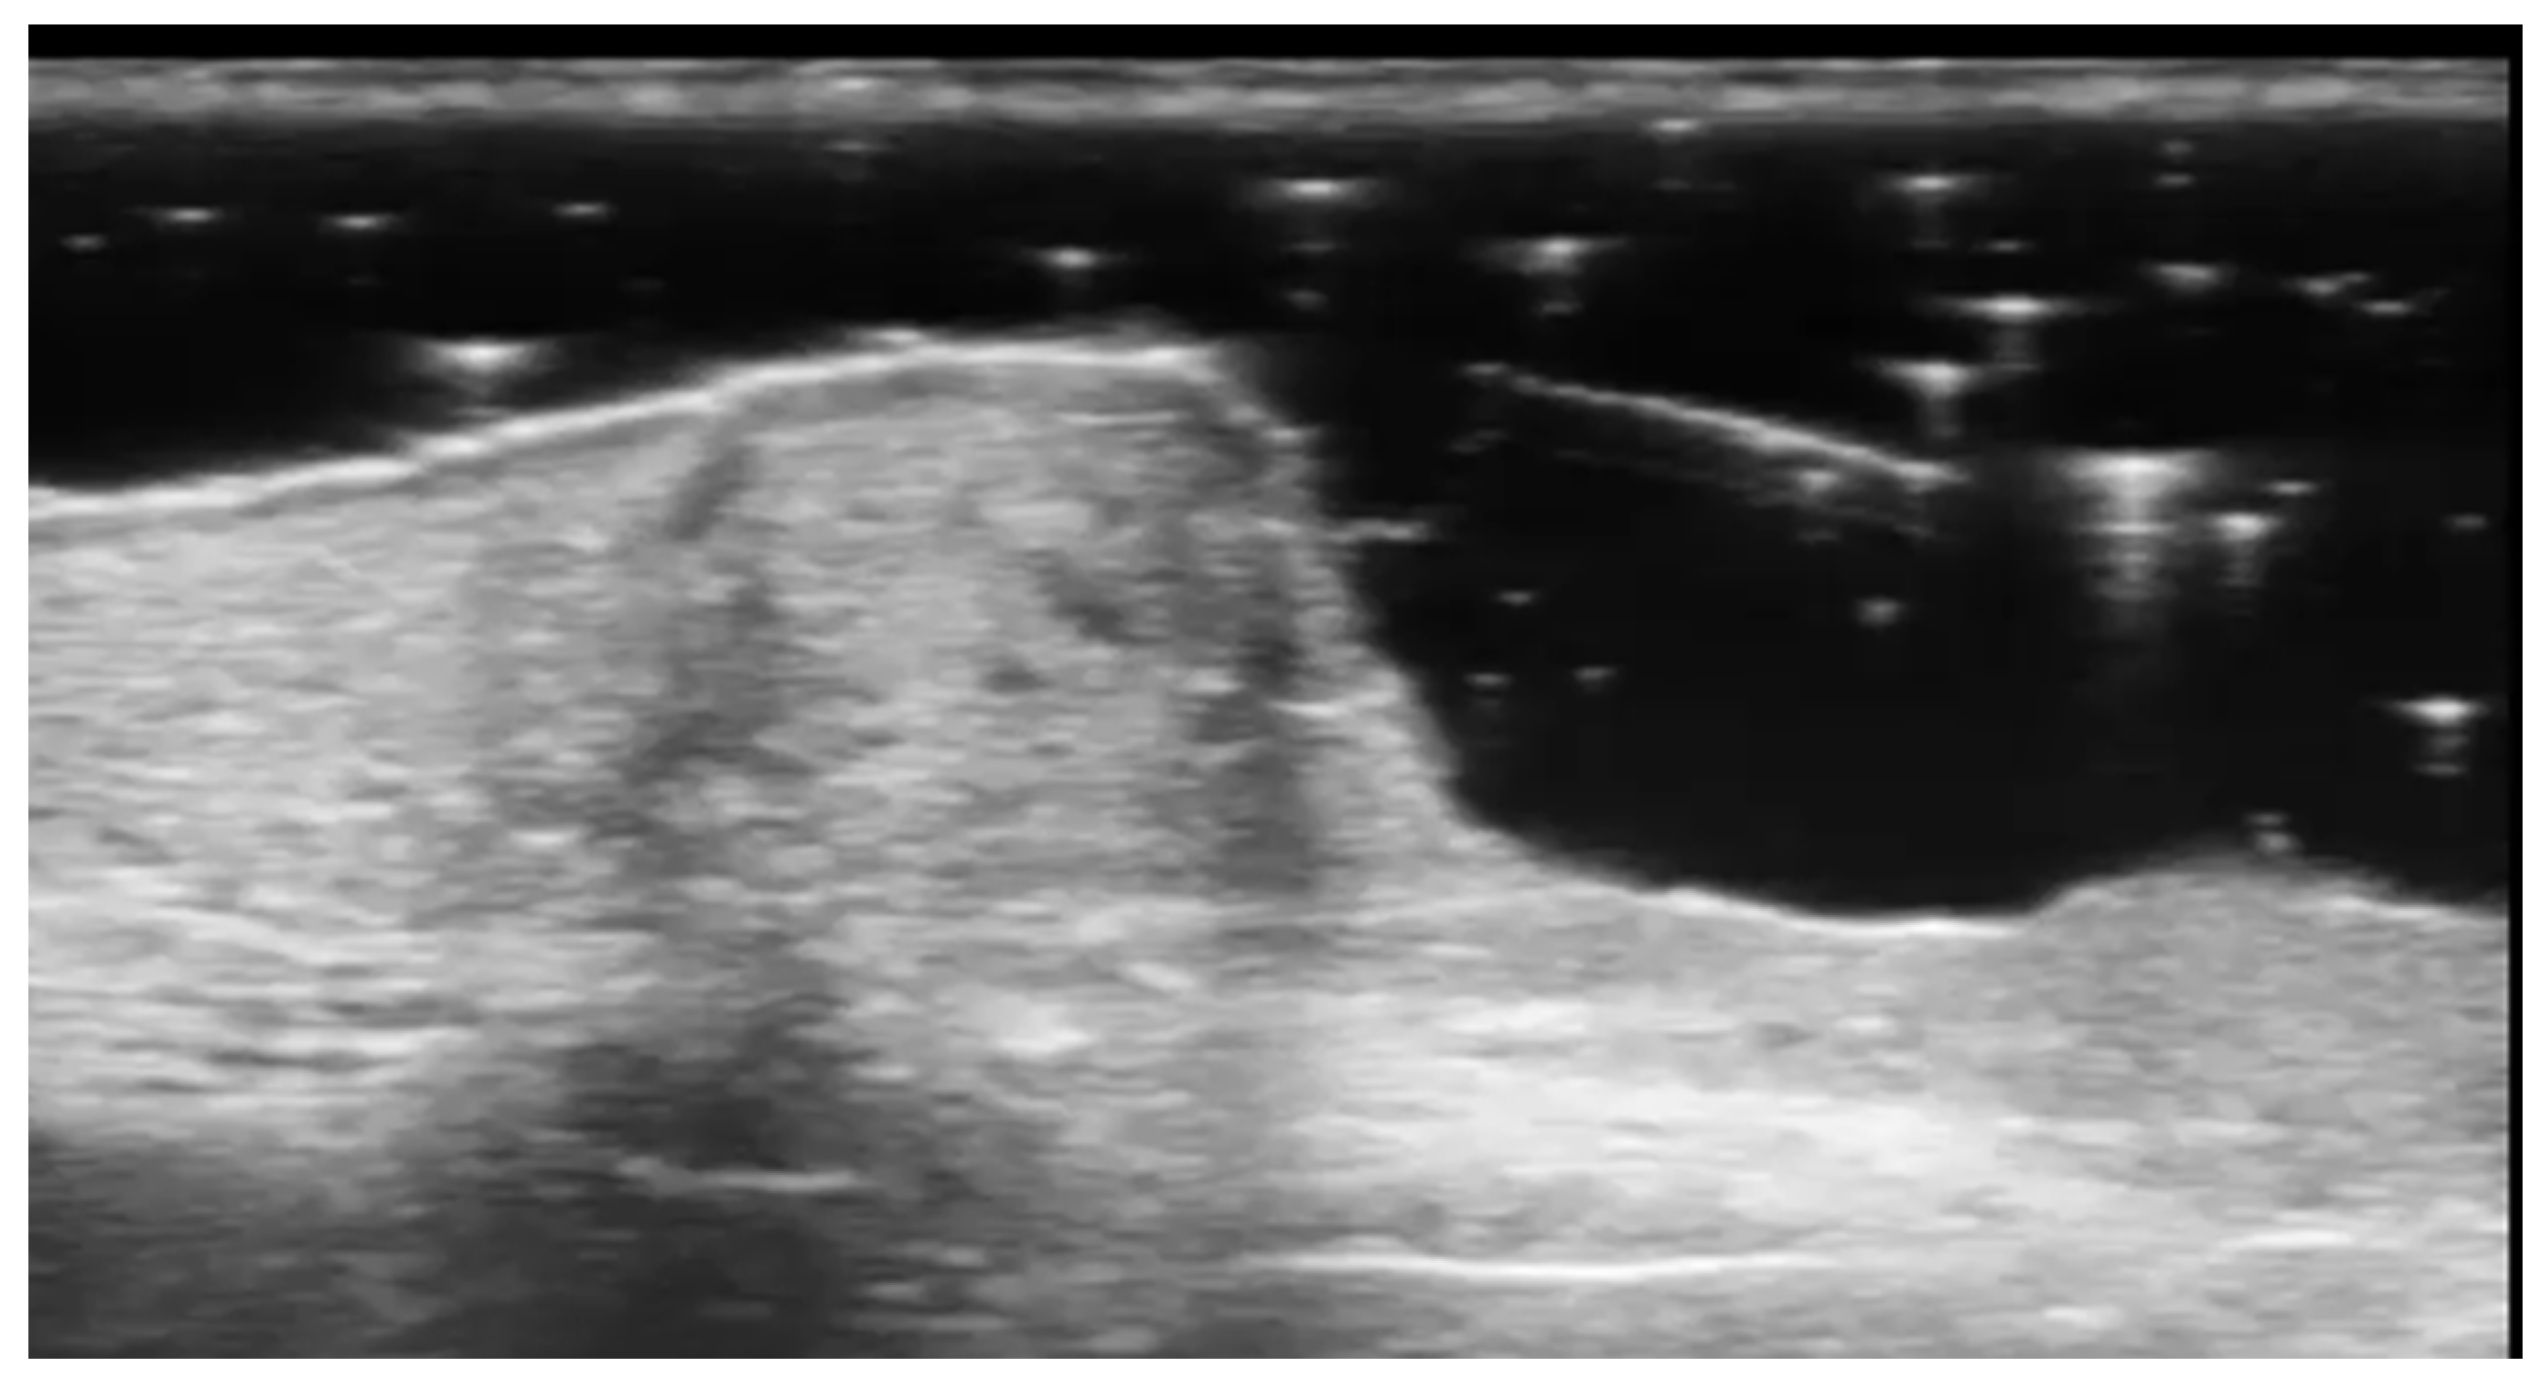

- Berritto, D.; Iacobellis, F.; Rossi, C.; Reginelli, A.; Cappabianca, S.; Grassi, R. Ultra high-frequency ultrasound: New capabilities for nail anatomy exploration. J. Dermatol. 2017, 44, 43–46. [Google Scholar] [CrossRef]

- Szymoniak-Lipska, M.; Polańska, A.; Jenerowicz, D.; Lipski, A.; Żaba, R.; Adamski, Z.; Dańczak-Pazdrowska, A. High-Frequency Ultrasonography and Evaporimetry in Non-invasive Evaluation of the Nail Unit. Front. Med. 2021, 8, 686470. [Google Scholar] [CrossRef]

- Sechi, A.; Wortsman, X.; Tosti, A.; Iorizzo, M. Advances in image-based diagnosis of nail disorders. J. Eur. Acad. Dermatol. Venereol. 2024; online ahead of print. [Google Scholar] [CrossRef]